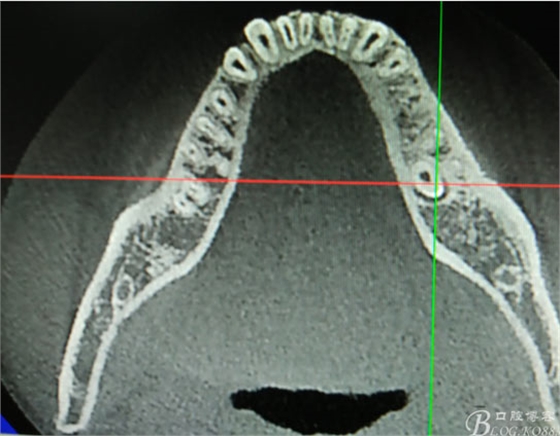

患者、盧xx、男、19歲。主訴:左側(cè)下頜乳磨牙未脫落,要求檢查。??茩z查:左側(cè)下頜第二乳磨牙有充填物。無松動(dòng),全景片檢查。35移位至36、37之間。頰舌側(cè)均不能觸及隆起。CBCT檢查:35位于36、37的舌側(cè)。表面骨質(zhì)約2mm左右。35完全骨埋伏,36的遠(yuǎn)中牙根疑是吸收。建議35暫觀察。置留不取。患者要求拔除擔(dān)心壓迫36牙根或者發(fā)生囊性變。術(shù)前簽手術(shù)同意書。